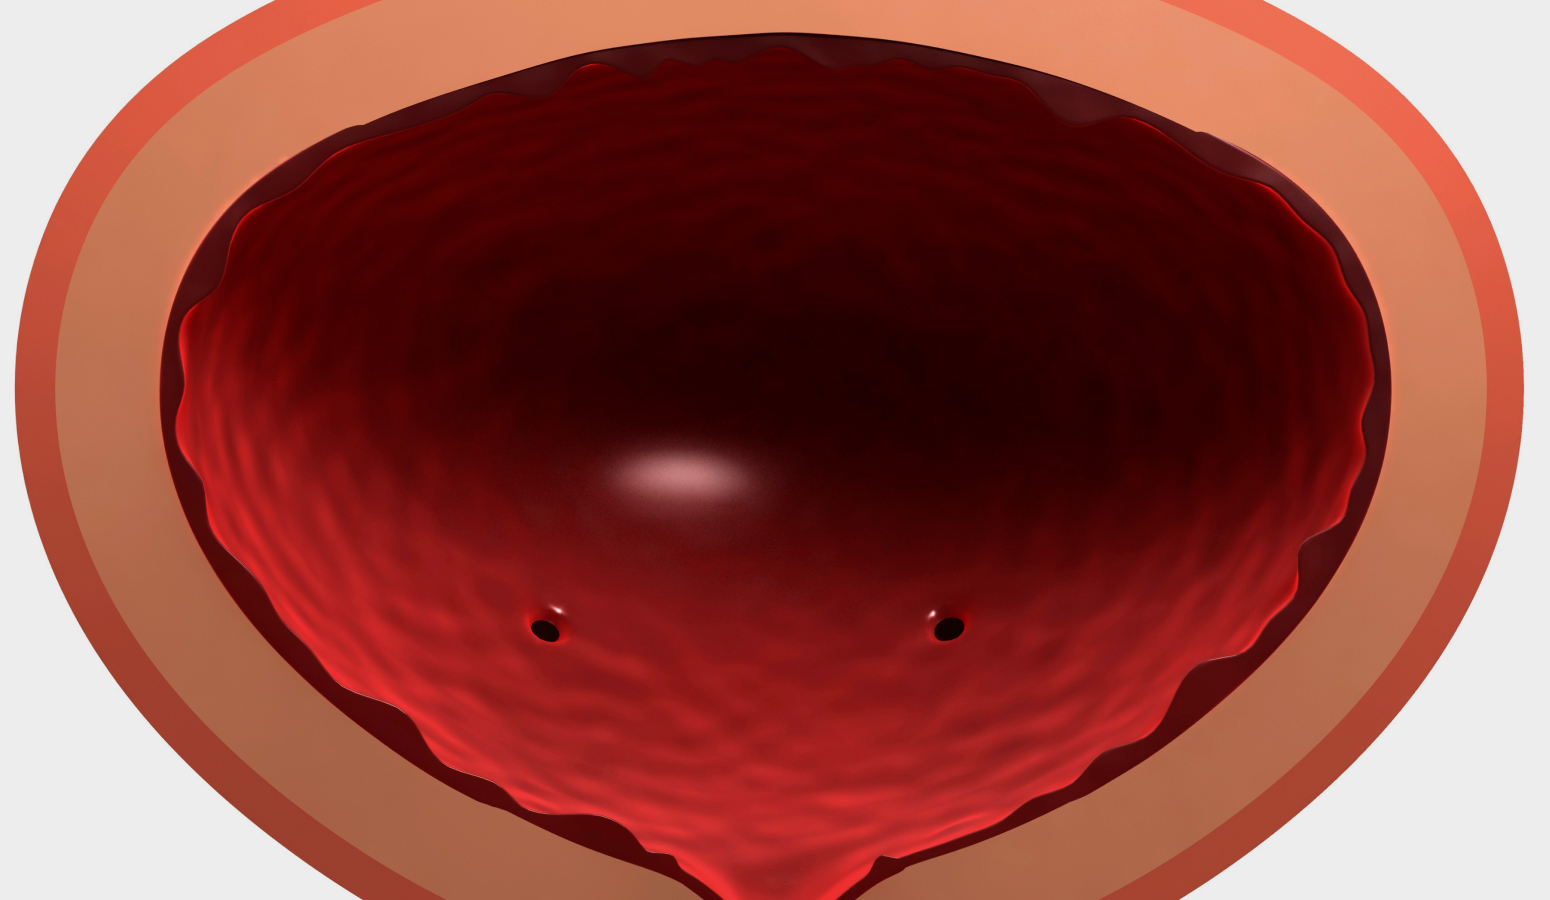

간질성 방광염

구상화 병변

구상화 병변간질성 방광염